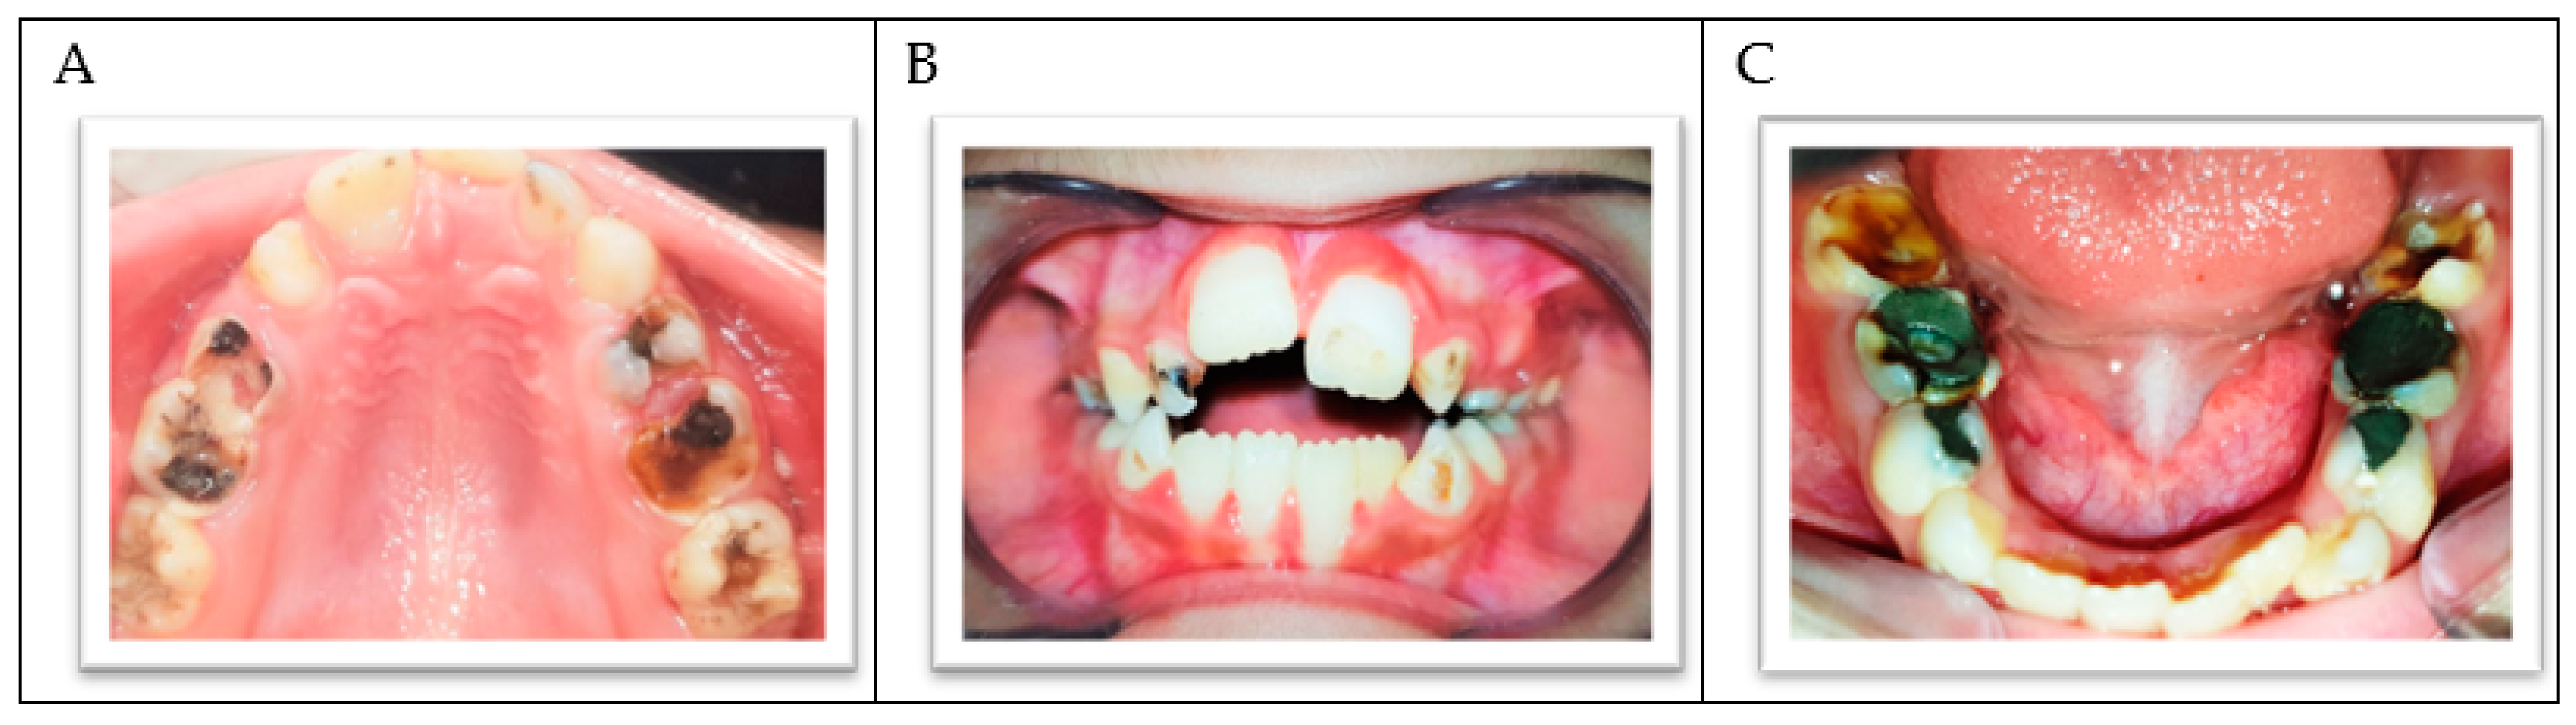

2. Case Report

| Special health needs Visible cavitations Enamel demineralization or hypomineralization Lowsocioeconomic status Insufficient oral hygiene measured with the aid of a plaque score High sugar intake measured by a dietary chart Medications that impair saliva flow (Tegretol) Poor toothbrushing performed only on days of dental treatment |